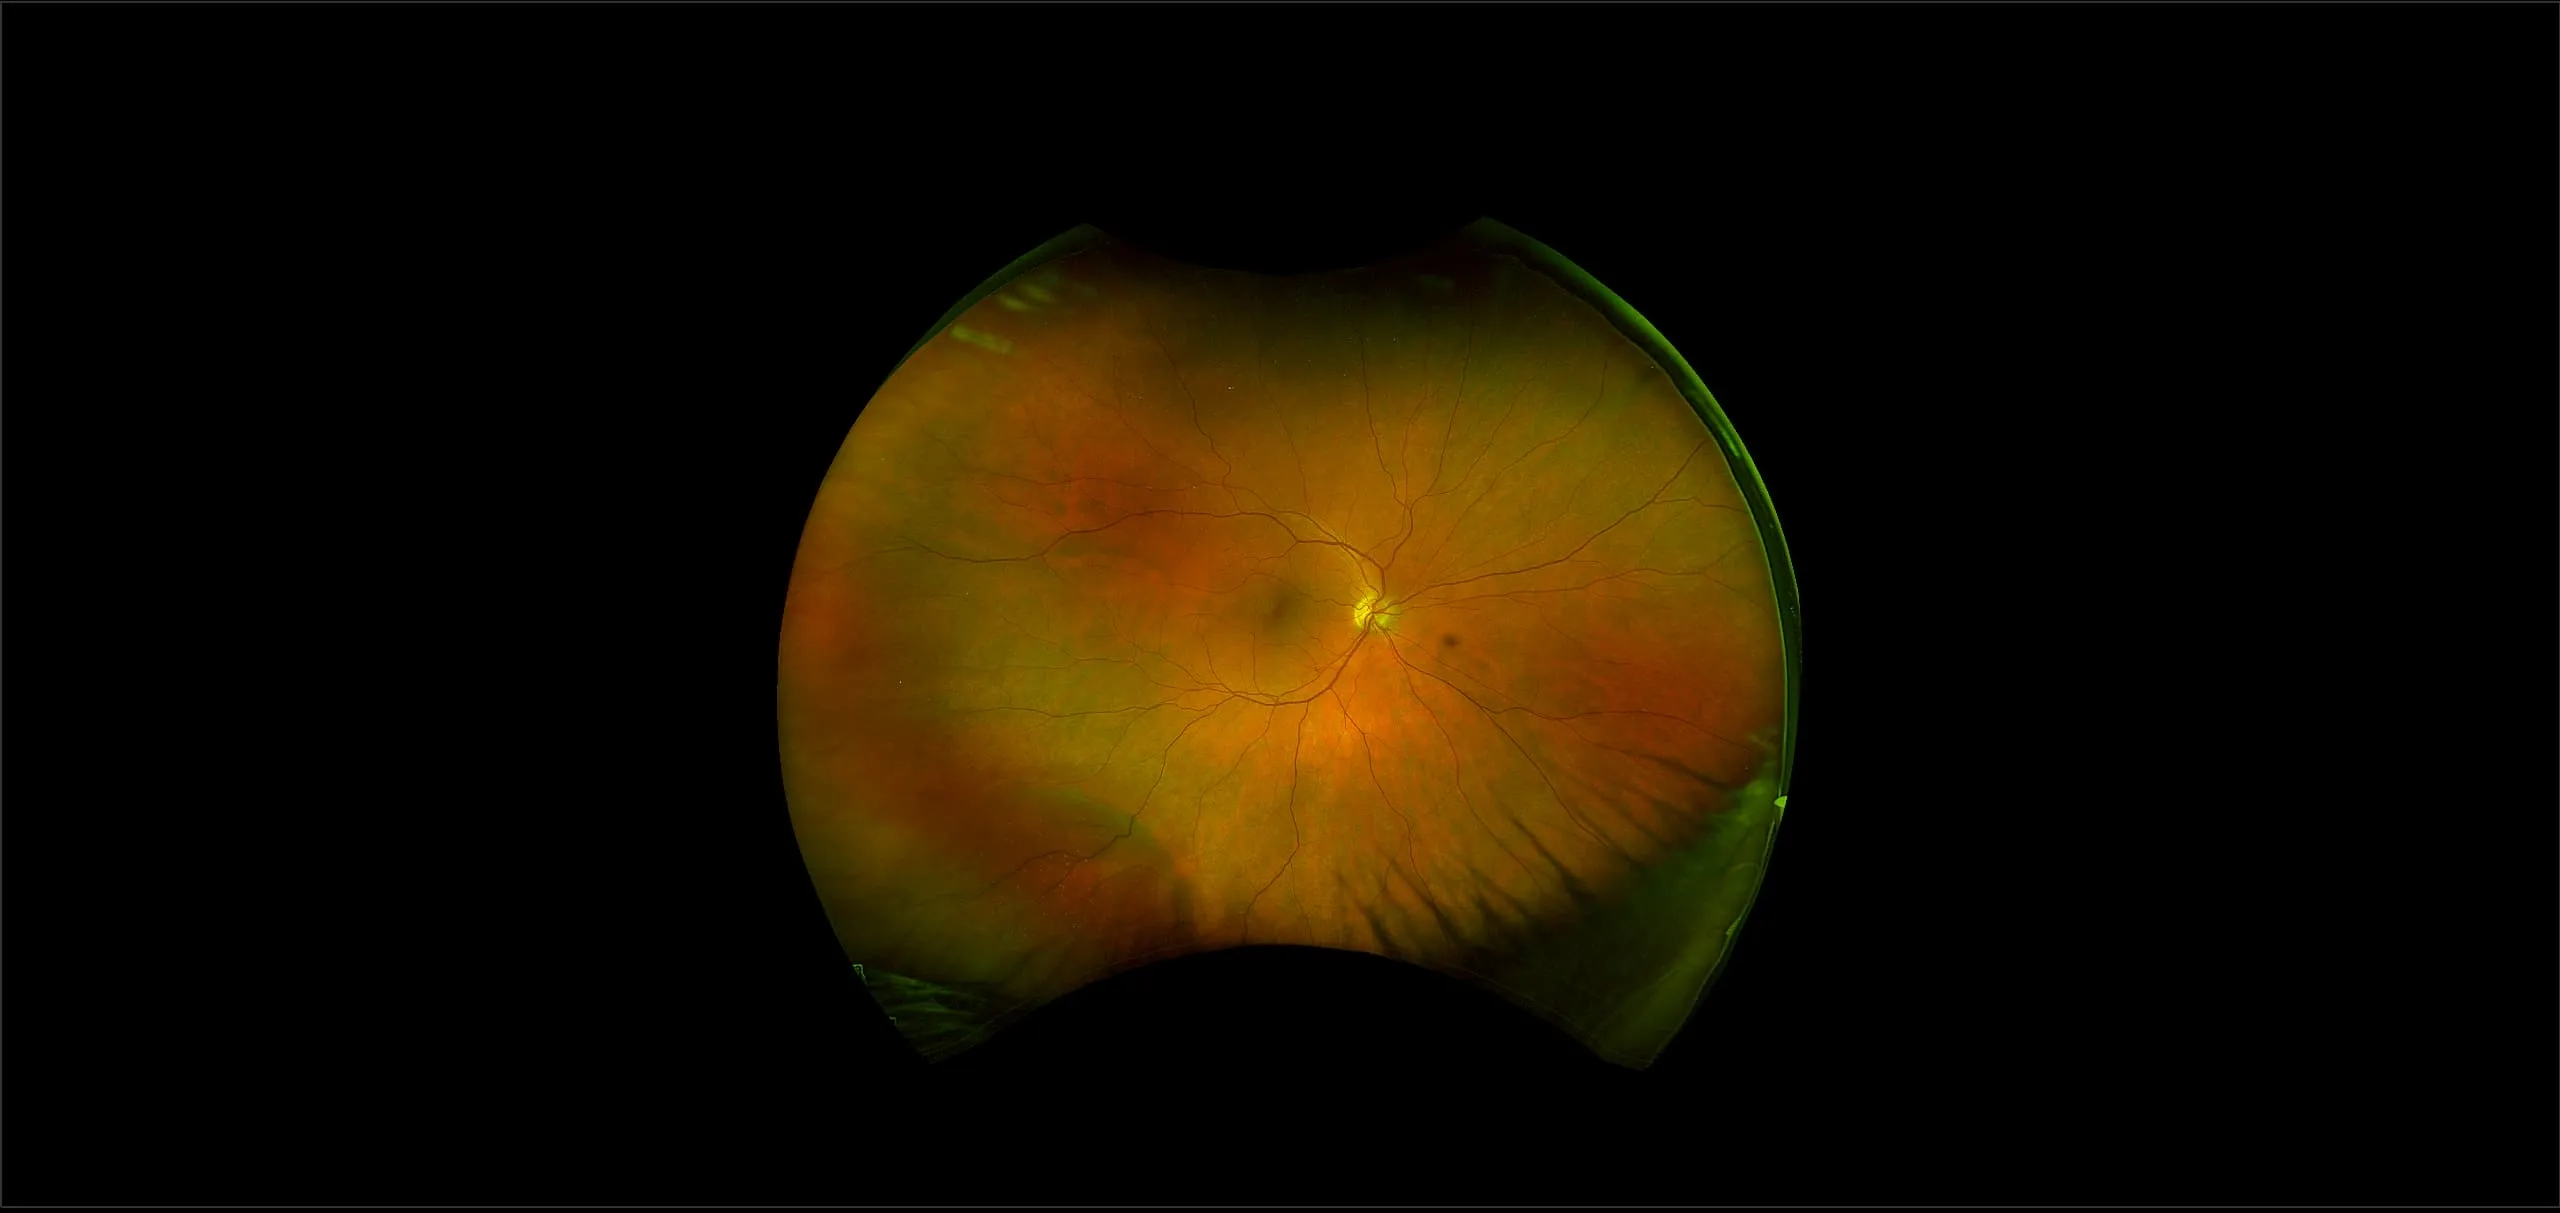

optomap® Recognizing Pathology

This material is designed as a searchable reference resource to support clinical decision-making. The information contained here should be used as general guidance when viewing optomap and OCT images from Optos devices. The differential diagnosis should be made under the direction of the responsible physician. These images were taken on the latest ultra-widefield optomap devices.

The Cases and Images

optomap Recognizing Pathology is searchable by pathology and/or optomap image modality. You may search by multiples of each selection. Each individual case is represented by the accompanying thumbnail image. Most cases include several different optomap image modalities. To view a full description of the case, please click on the thumbnail. Each image in the case will be made available through our OptosAdvance software which provides multi-dimensional visualization of digital images to aid in the analysis of anatomy and pathology. Support and pathology definitions can be found by selecting one of the buttons, above. Should you have questions, please complete the form below.